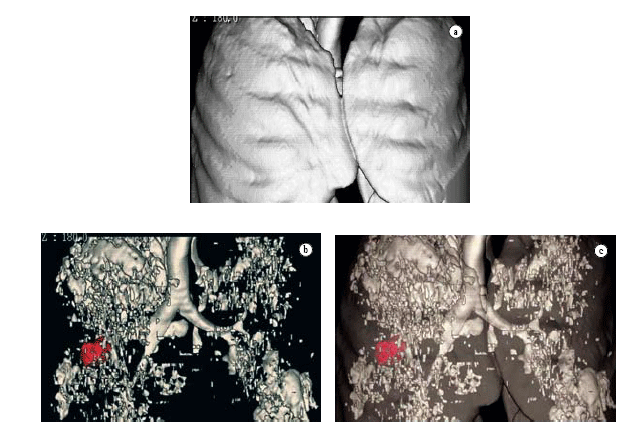

The acquisition of data volume in a single breath-hold allows us to reconstruct data in three-dimensional format, using three-dimensional CT. This technological resource has been more frequently used in the investigation of chest alterations.(51-56) One of the pioneers in the dissemination of the technique(56) demonstrated its efficiency in the quantification of emphysema. The denomination three-dimensional CT-guided densitometry and volumetric assessment for emphysema(55) has been currently suggested for this quantification process of the volume of emphysema, based on data obtained through spiral CT scan with three-dimensional representation of emphysematous lesions (Figures 5 and 6). The test measures the whole pulmonary volume with abnormal density and, also, the whole lung volume with normal density,(41,56-61) setting them apart based on the separation threshold generally selected at −950 HU, as per the suggestion of one author. Among the practical applications of the technique, one study demonstrated that normal CT-guided pulmonary densitometry and volumetric assessment excels HRCT, and should be included in the preoperative evaluation of patients for whom surgery for volumetric reduction of the lungs has been indicated.(58) This clinical applicability of three-dimensional CT-guided densitometry and volumetric assessment used for the same purpose has been known in Brazil for some time.(39) In a recent consensus, the use of three-dimensional CT-guided densitometry and volumetric assessment was suggested for the evaluation of therapeutic efficacy in the treatment of emphysema, replacing FEV.(59)

The evaluation of advantages of three-dimensional CT-guided densitometry and volumetric assessment for therapeutic decision in patients with operable pulmonary carcinoma from the point of view of tumor-node-metastasis staging is under study. However, with borderline pulmonary function. Figure 7 exemplifies a case in which the

neoplastic lesion (in red) is found, by unfortunate and common chance, in the lobe that was less affected by emphysema. In this case, lower right lobectomy will be almost equivalent to pneumonectomy, since the right upper lobe, which would be the remaining lobe, is almost completely compromised by emphysema.